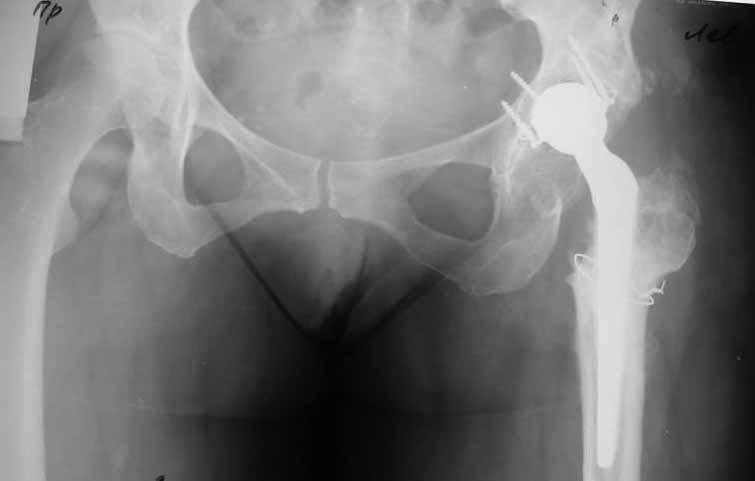

Уважаемые коллеги. Хотелось бы услышать мнения и советы по представляемому случаю.

области левого тазобедренного сустава. При рентгеновском и КТ исследованиях (июль с.г.)

нестабильность тазового компонента. От предложенной замены протеза пациентка на тот

по песку на пляже, носила тяжести). Ежедневно принимала диклофенак. На рентгенограммах

переломы правой лонной кости. Сейчас госпитализирована из-за болей в паху справа. Боли

-Можно ли так же расценить ситуацию на стороне протеза и, соответственно, не

торопиться с ревизией, рассчитывая на вторичную стабилизацию? Уж больно не хочется менять

-Если думать о ревизии, то когда? На представленных снимках тазобедренный сустав до и

сразу после операции, затем 2 снимка 2009г., когда ничего не беспокоило, затем КТ 2-х

месячной давности и вчерашние рентгенограммы обоих тазобедренных суставов.